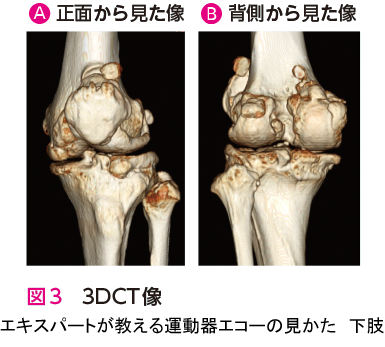

人工関節置換術を施行した症例です.エコー検査での膝関節前方(長軸像)では,膝蓋骨の骨棘と関節水腫を観察できます.また,膝関節内側(長軸像)では,内側側副靭帯浅層の直下に骨棘と内側半月板を観察できます.骨棘は大腿骨と脛骨から大きく張り出しています(図1🅑*).